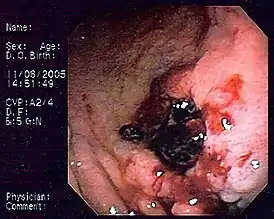

![]() MALT-лимфома желудка | |